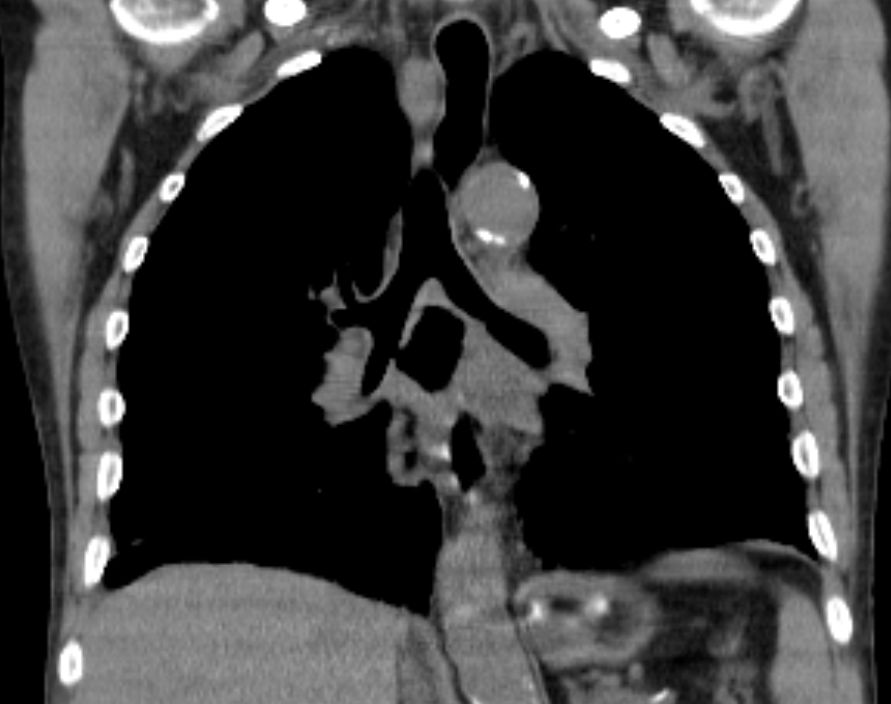

CT Infiltration des oberen Mediastinums. Flottierender Thrombus in der Vena cava superior.